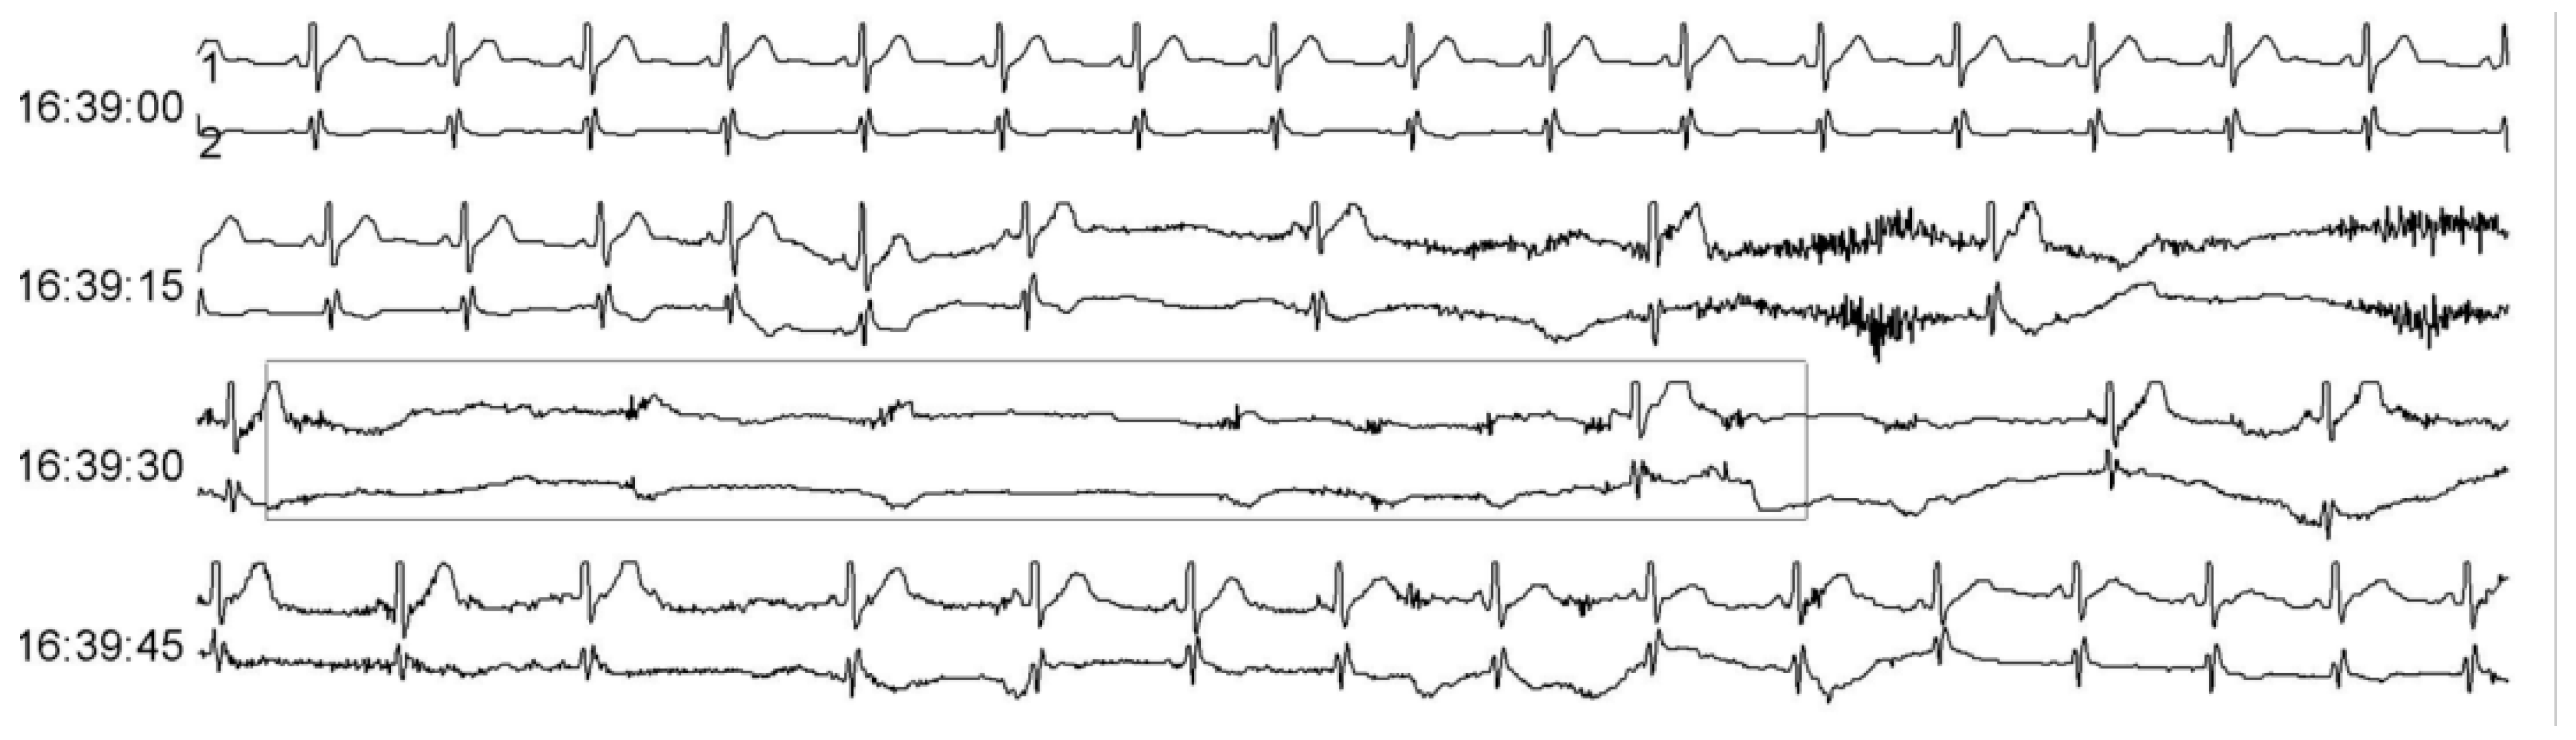

A 45-year-old man presented with acute onset of hiccups and vomiting for nearly two weeks prior to admission. Gastrointestinal endoscopy revealed chronic superficial gastritis, and infection-related tests were negative. The cause of the hiccups remained unclear, while metoclopramide, haloperidol, and chlorpromazine did not relieve the hiccups and vomiting. He had no past medical history, and the results of his vital signs included a blood pressure of 91/56 mmHg, a pulse of 48 bpm, and a normal sinus rhythm. No other abnormal pulmonary, cardiac, or abdominal findings were confirmed, while the results of his neurological examination were normal, except for bilaterally absent deep tendon reflexes. During hospitalization, he had slow heart rates that ranged from 30 to 60 bpm with several episodes of syncope. Moreover, ECG monitoring indicated the occurrence of sinus pauses with a duration of about 10 s, while Holter monitoring showed recurring cardiac arrest with the longest RR interval of 11 s (Figure 1). He was subsequently diagnosed with SSS, before temporary pacemaker implantation surgery was performed.

Figure 1.

Holter monitoring showing sinus arrest with the longest RR interval at about 10 s.